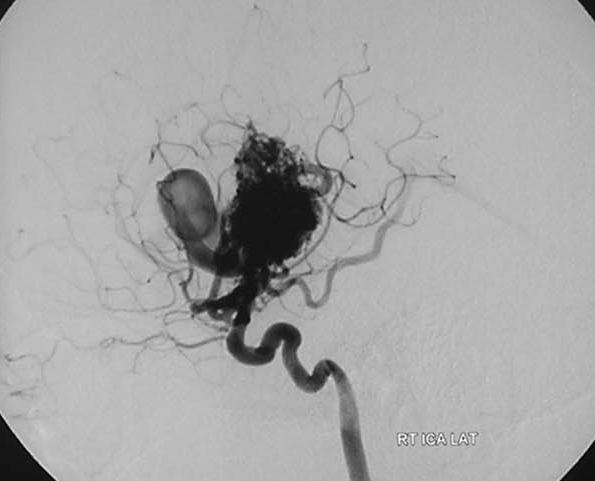

Arteriovenous malformations

Arteriovenous malformations of the brain are abnormal bunch of blood vessels that can rupture causing bleeding, or may cause seizures. Brain imaging (CT, MRI) is required for early diagnosis, while definitive treatment is carried out after cerebral angiography. Treatment implies craniotomy and excision of the AVM, which can be done safely in majority of the cases. Embolisation and radiosurgery are acceptable substitutes, but carry risk of further bleeding.